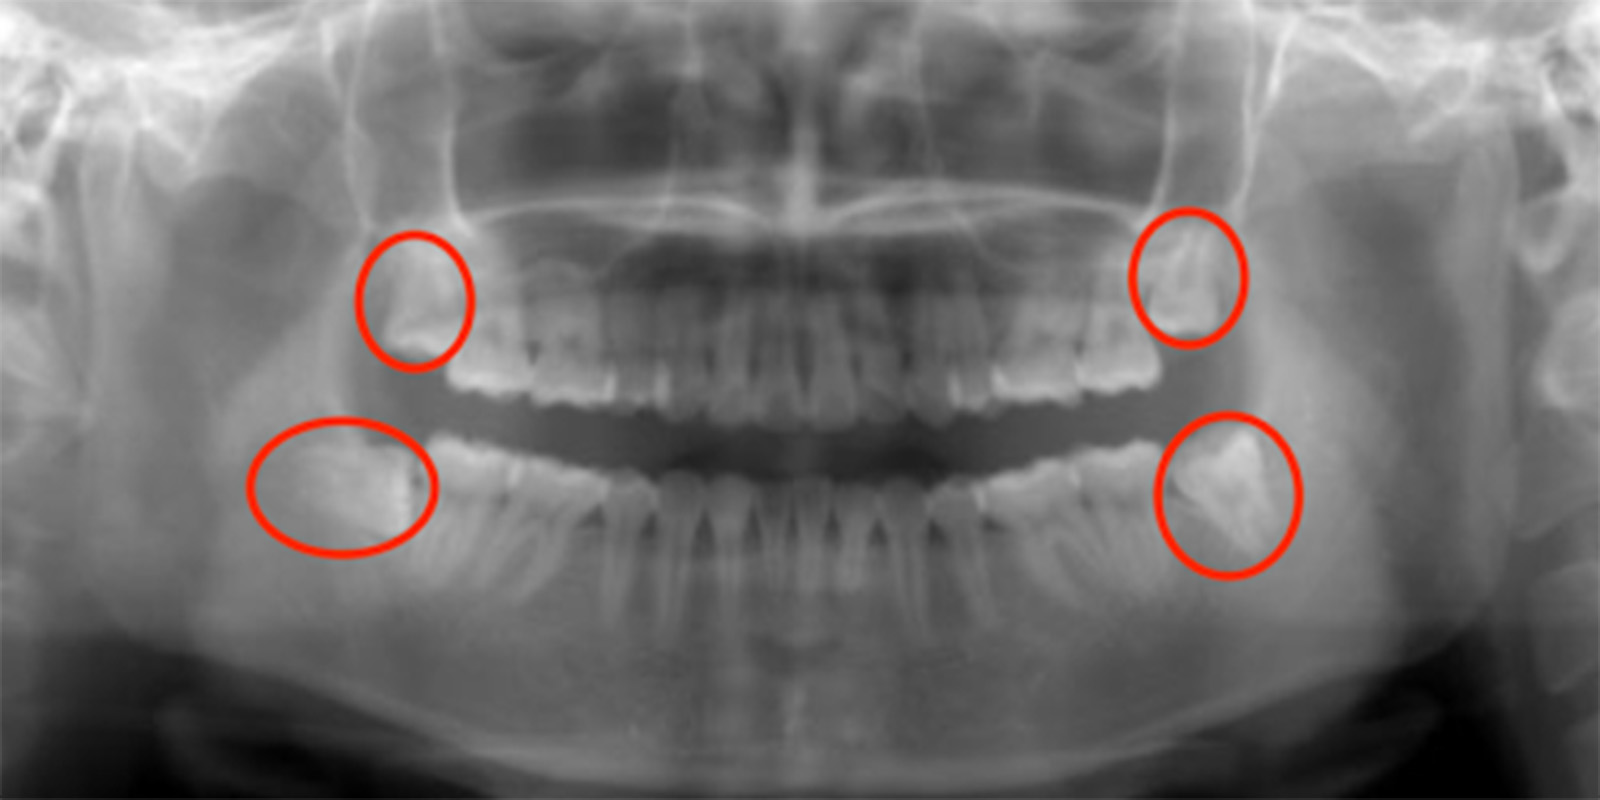

親知らずがあるレントゲン画像

ただ根の先に下顎管が触れているようなケースであれば2回で対応したりしますが歯の頭の部分が下顎管と触れているような稀なケース、親知らず周りが嚢胞になってしまっているケース、全身疾患がある方、外科処置が困難な方に関しては大学病院を紹介させていただくこともあります。